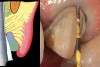

Figure 1  View of 4 porcelain veneer preparations with the margins placed at the level of tissue.

Figure 1

Figure 2  Note the invisibility of the marginal line in the completed veneers, even though the margin has not been carried below tissue.

Figure 2

A clinician is faced with 3 options for for margin placement when considering an anterior esthetic restoration: supragingival, equigingival (ie, even with tissue), and subgingival.1 The supragingival or equigingival margin will have the least impact on the periodontium and, classically, was only used in nonesthetic areas because of the stark contrast in color and opacity of traditional restorative materials. With the advent of adhesive dentistry, resin cements, and more translucent restorative materials, the ability to place supragingival or equigingival margins even in esthetic areas is now a reality (Figure 1 and Figure 2). The primary requirement of a material to enable its use in esthetic areas supra- or equigingivally is a high level of cervical translucence. Materials such as feldspathic porcelain, as well as pressable ceramics, meet this requirement. Consequently, whenever possible, these restorations should be chosen not just for their esthetic advantages, but for their favorable periodontal impact as well. The greatest biologic risk occurs when placing subgingival margins.2